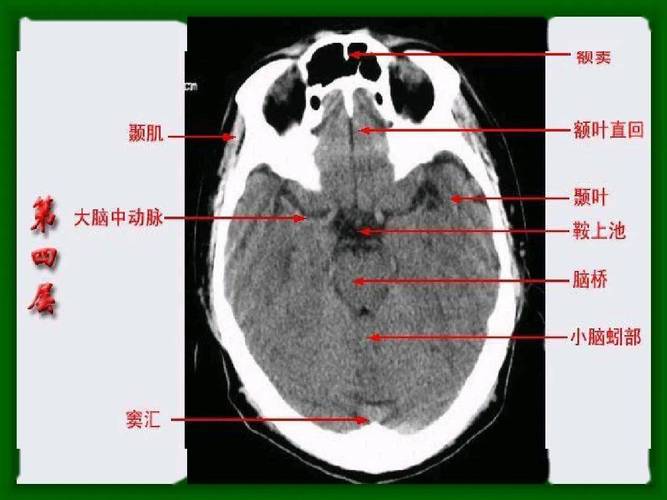

头部CT解剖

头部CT解剖,头部CT解剖

头颅ct断层解剖

影像医生必须掌握的头颅ct解剖与常见出血梗死判读

头颅ct影像解剖

头颅ct 解剖图谱,人手一份

正常头颅ctppt

头颅ct解剖

颅脑ct解剖